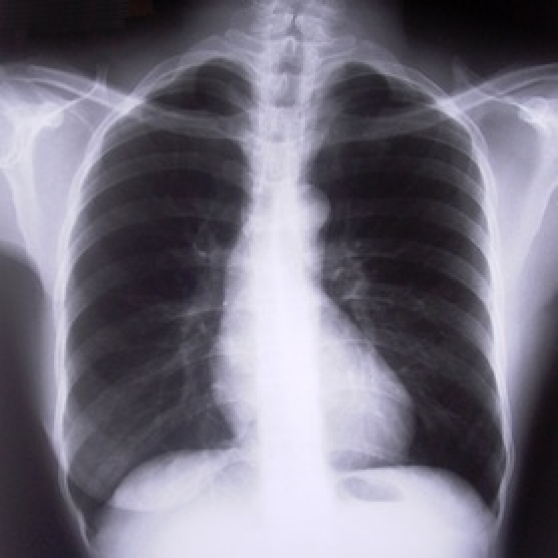

COPD is the most common reason for a lung transplant. Lung transplants are done in large hospitals called medical centers where the staff has a lot of experience in dealing with organ transplants. Talk to your doctor about treatment options for COPD.